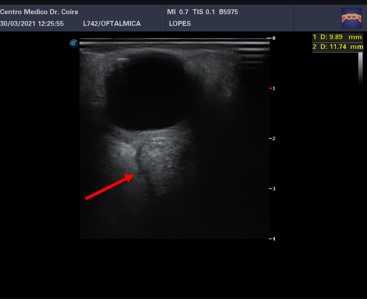

Imágenes E y F: ecografía ocular derecha: a nivel retroorbitario en el ojo derecho y en el área correspondiente a la inserción del nervio óptico, se observa una imagen asimétrica con relación al contralateral de ecoestructura sólida ubicada en la vaina del nervio óptico las medidas 11,7 x 9,8 mm.